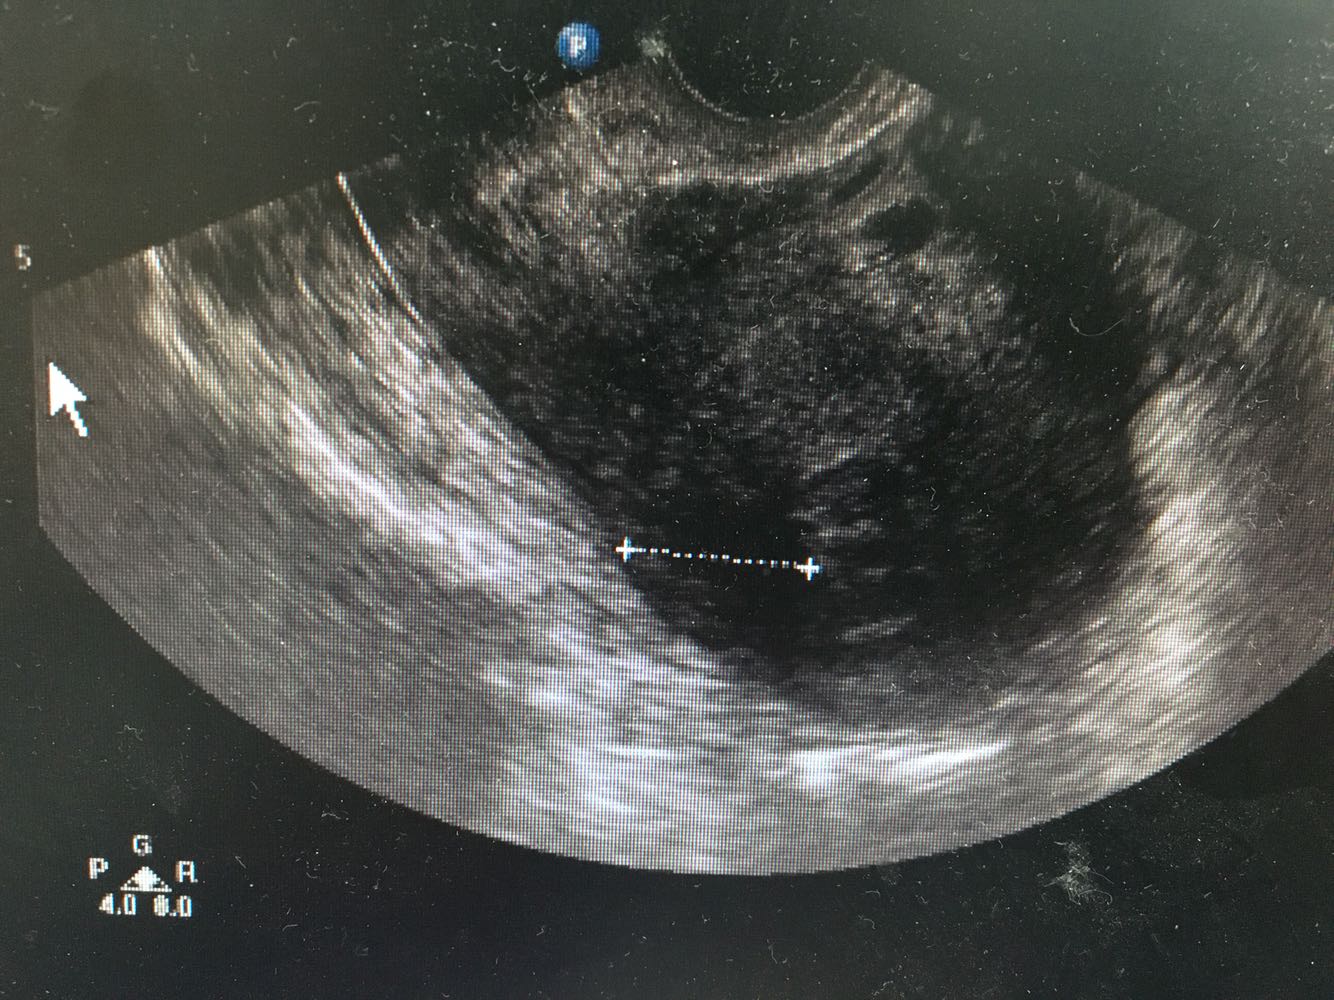

1、患者,女性,55岁 2、主诉:发现子宫肌瘤5年,伴进行性增大伴半年 现病史:1-0-2-1,初潮16岁,平时月经规律,6/28天,量中,痛经(±),LMP:2017-2-13。患者2015年体检时发现子宫肌瘤(具体报告未见),当时月经量无增多,偶伴痛经,偶伴腹胀感,无下腹疼痛感,无头晕乏力,无腰酸背痛,无异常阴道流血流液,存在白带增多伴异味,无尿频尿急。之后定期复查体检发现子宫进行性增大,半年前妇科B超:可见数个最大约67*60*56mm的低回声团块,界清,内部回声不均匀,提示子宫肌瘤,患者自觉尿频,每日小便10多次,夜间小便1次,有尿不净感,偶有腰酸、肛门坠胀感,建议患者手术治疗,为求进一步诊疗,遂就诊门诊,门诊拟“子宫肌瘤”收治。 3、既往史:妇科炎症30余年,白带量多,有异味,否认其他慢性病史

诊断:子宫肌瘤 诊疗计划:入院后完善检查,排除禁忌症后,行经腹全子宫切除术+盆腔粘连松解术。探查见子宫不均匀增大如孕3+月,左侧附件与左盆腔壁呈面膜性粘连,予分解黏连,术后予抗炎补液等对症支持治疗,术后恢复可,切口愈合良好,II/甲,阴道无流血流液。